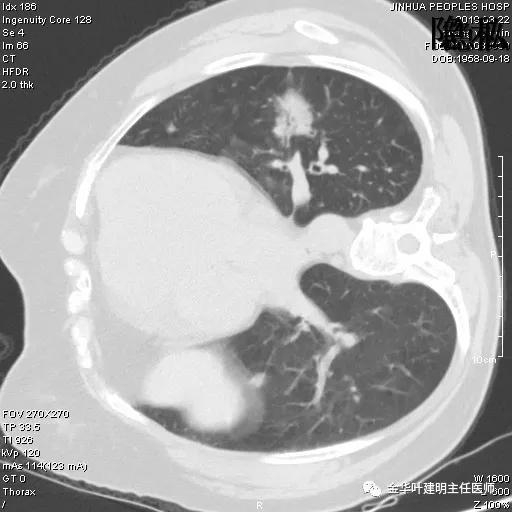

可见左肺下叶比较靠中央的部位也有一病灶,是混合磨玻璃影,偏实性,瘤肺边界清楚,是较为典型的肺癌表现。进一步的靶扫描图像如下:

靶扫描更清晰的显示细节,从影像上看,基本可以断定左下肺的是恶性肿瘤了,而且已经密度较高,长径也在3厘米以上,不能继续观察等待了!